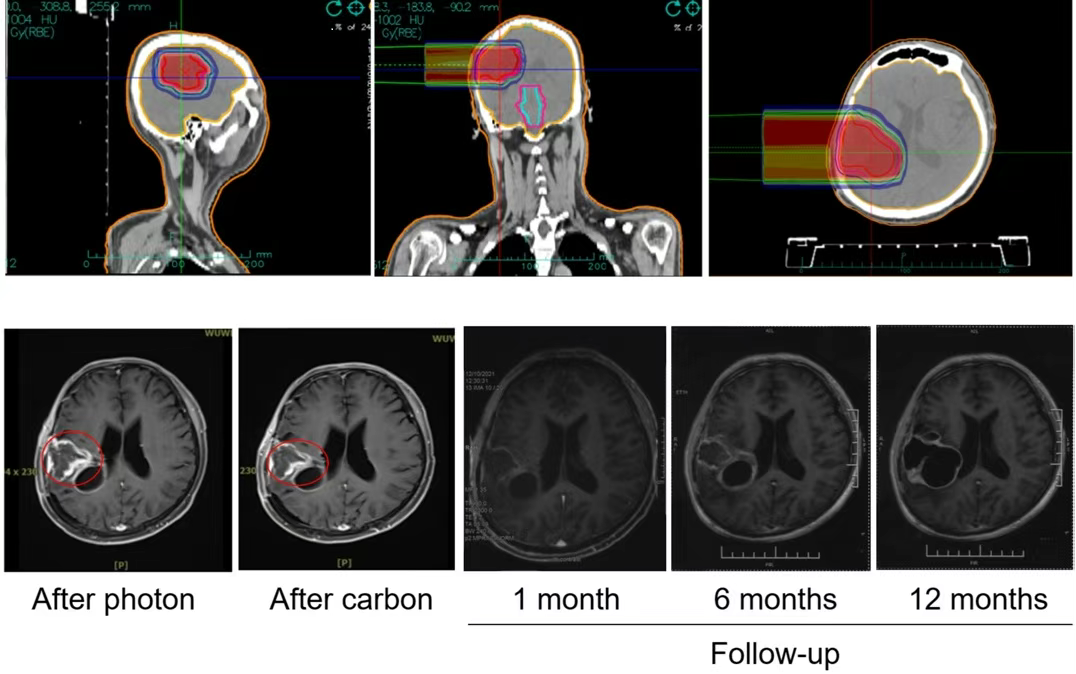

Figure: Dose distribution map for a glioma patient treated with heavy ion radiotherapy, showing increased dose to the tumor area and reduced radiation damage to normal brain tissue.